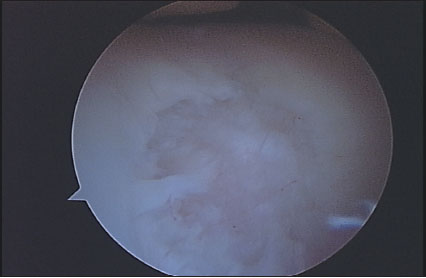

Todos los pacientes que realizaron su RM de rodilla en el Servicio de Diagnóstico por Imágenes del Hospital Británico, y luego fueron operados de su rodilla en el mismo Centro durante el mes de Abril de 2009, fueron incluidos en el presente trabajo. Es un estudio con un diseño transversal, con recolección de datos retrospectiva, nivel de evidencia III. Un total de 43 pacientes fueron incluidos. Dos pacientes fueron excluidos del análisis por alteración de la imagen de resonancia, uno por artefacto del movimiento durante el estudio y el otro por artefacto producido por material de osteosíntesis colocado en la rodilla en una intervención previa. De los 41 pacientes evaluados en el estudio, el promedio de edad fue de 50 años (21-71). Fueron 27 hombres y 14 mujeres evaluados. El intervalo de tiempo promedio entre la realización de la RM y la cirugía fue de 63 días (6-275 d). Veintinueve pacientes (70,73 %) fueron intervenidos dentro de los 2 meses de realizada la RM. Se realizó una revisión de las historias clínicas para corroborar que ningún paciente refirió alguna lesión durante ese intervalo de tiempo. En todos los casos se realizó una RM con un equipo Philips de 1,5 Tesla, realizando en todas ellas cortes de reconstrucción axial, coronal y sagital, para evaluar adecuadamente la articulación en toda su extensión. Cada estudio de RM fue analizado en forma retrospectiva por dos observadores ciegos de los resultados obtenidos luego en la cirugía, ambos trabajaron en forma conjunta. Uno de los evaluadores (M.C) es médico de planta del Servicio de Diagnóstico por Imágenes del Hospital (especialista en RM músculo esquelética); el otro evaluador (L.C) es Jefe de Residentes de Diagnóstico por Imágenes del Hospital. Ambos estudiaron cada caso en particular, y debían valorar el cartílago en cada zona articular y establecer un único resultado. Seis superficies articulares fueron evaluadas: rótula, tróclea, cóndilo femoral medial y lateral, platillo tibial medial y lateral. El cartílago articular fue clasificado en la RM y en la artroscopia de acuerdo a la clasificación de Johansson. (7) El Grado 0 indica cartílago intacto; grado 1 ablandamiento o edema de cartílago; grado 2 fibrilación de cartílago; grado 3 ulceración superficial o fisura que comprometen menos del 50% del espesor del cartílago; grado 4 ulceración profunda o fisuras que comprometen ás del 50% del espesor de cartílago; grado 5 lesión de espesor completo con hueso expuesto; grado 6 lesión en espejo, con hueso expuesto en ambas superficie enfrentadas. Todas las lesiones condrales debieron ser confirmadas en al menos 2 cortes de RM. Se confeccionó en cada caso un registro escrito de cada paciente con los grados de lesión condral en cada superficie. (Ver Figs. 1 a 4)

Figura 4: Lesión condral de espesor completo. Corresponde a un grado 5.